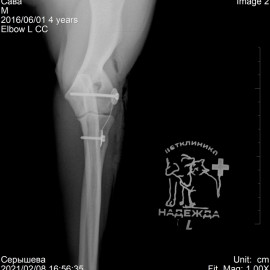

Обратились с жалобами на остро развившееся отсутствие опороспособности на левую переднюю лапу после прогулки. После исследований был поставлен диагноз: медиальный вывих левого локтевого сустава. Была проведена операция: остеосинтез левого локтевого сустава. Был установлен протез латеральной коллатеральной связки.

Снимки 2-3 после операции